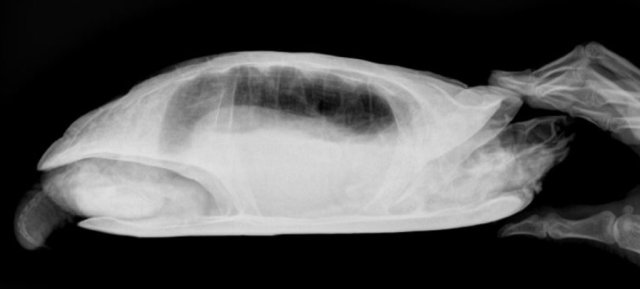

Елена_F Ваше имя: Цып Локация: Россия. г.Курск Опубликовано: 20 марта 2025 Автор Опубликовано: 20 марта 2025 @moth А по рентгену можно что- то сказать? Вроде газов меньше стало.

Консультанты moth Ваше имя: Мария Локация: Москва Опубликовано: 20 марта 2025 Консультанты Опубликовано: 20 марта 2025 @Елена_F врач расшифровку рентгена ещё не делала? по мне лучше стало, но надо чтобы врач смотрела и расшифровала, потому что здесь ошибка будет очень дорого стоить

Елена_F Ваше имя: Цып Локация: Россия. г.Курск Опубликовано: 20 марта 2025 Автор Опубликовано: 20 марта 2025 @moth Расшифровку она не делала, но для сравнения я ей показала старый снимок и она мне показала, что на новом снимке меньше затемнений, т.е. газы уходят. С сердцем тоже вроде всё нормально, осмотрела язык.